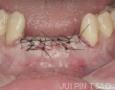

Baseline

Surgery